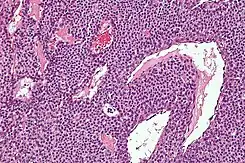

Microfotografía de un tumor glómico